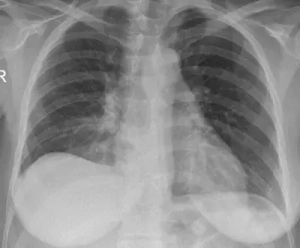

Moderate and large volume nonmalignant pleural effusions independently associated with AKI: Study

Moderate and large effusion volume nonmalignant pleural effusions…